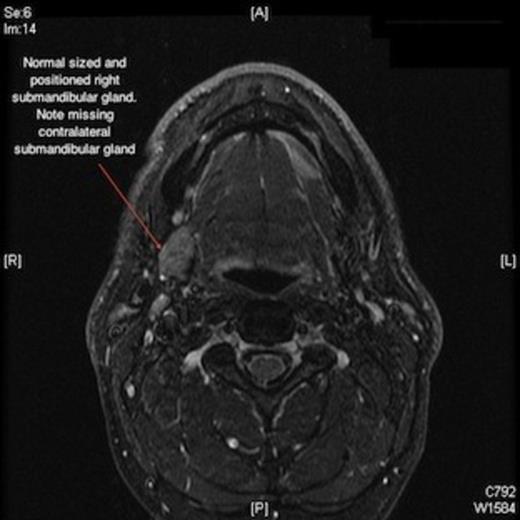

The clinical impression was of an enlarged sublingual gland, and so a fine needle aspiration was carried out. The cytology report confirmed salivary gland cells, some of which were enlarged. In view of this, a magnetic resonance imaging scan was ordered which confirmed a left anterior floor of mouth mass of 3 x 1 cm, (figures 1 and 2). Interestingly there was also a missing ipsilateral submandibular gland. The remaining major salivary glands were of normal appearance and dimensions.

Magnetic resonance imaging scan showing missing left submandibular gland